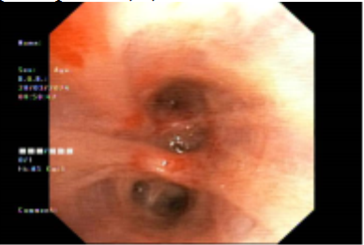

Hình 4: Hình ảnh chít hẹp lòng phế quản trên nội soi phế quản.